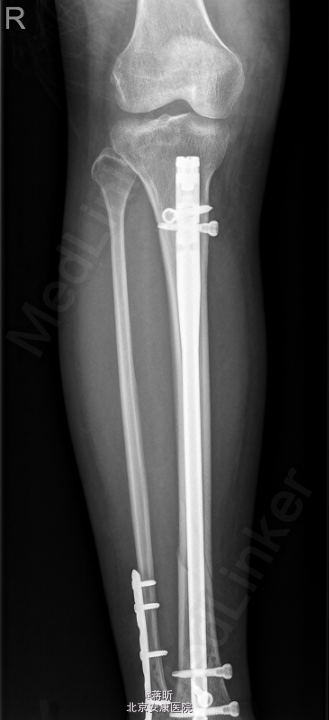

患者,女,32岁,因“右侧胫腓骨骨折术后1月余,发现下肢窦道1周”入院。 患者1月余前因外伤致右侧胫腓骨骨折,于2015-03-24在我院行“右胫骨骨折闭合复位内固定术+右腓骨骨折切复内固术”,术程顺利,术后恢复可,常规拍片复查,1周前自检发现右下肢膝关节处及外踝处出现窦道,伴流脓,无下肢麻木,无感觉异常,无发热寒战等其他不适,患者遂来我院就诊,门诊拟“骨折术后感染收住入院”。既往有“1型糖尿病”病史8年。

右小腿皮温稍高,右膝关节及踝关节活动未受限,右膝及右外踝处可见2处手术疤痕,分别长约7cm及5cm,愈合尚可,右膝正中及右外踝可见3处窦道,可见脓液流出,右足背动脉搏动可及,末梢各趾血循、感觉、活动正常。余肢体无殊。 2015-4-27我院拍片示:右胫骨中下段骨折术后复查。

初步诊断: 1,右胫腓骨骨折术后感染;2,1型糖尿病 处理:[右侧]胫腓骨骨折术后感染清创VSD+右踝内固定拆除术